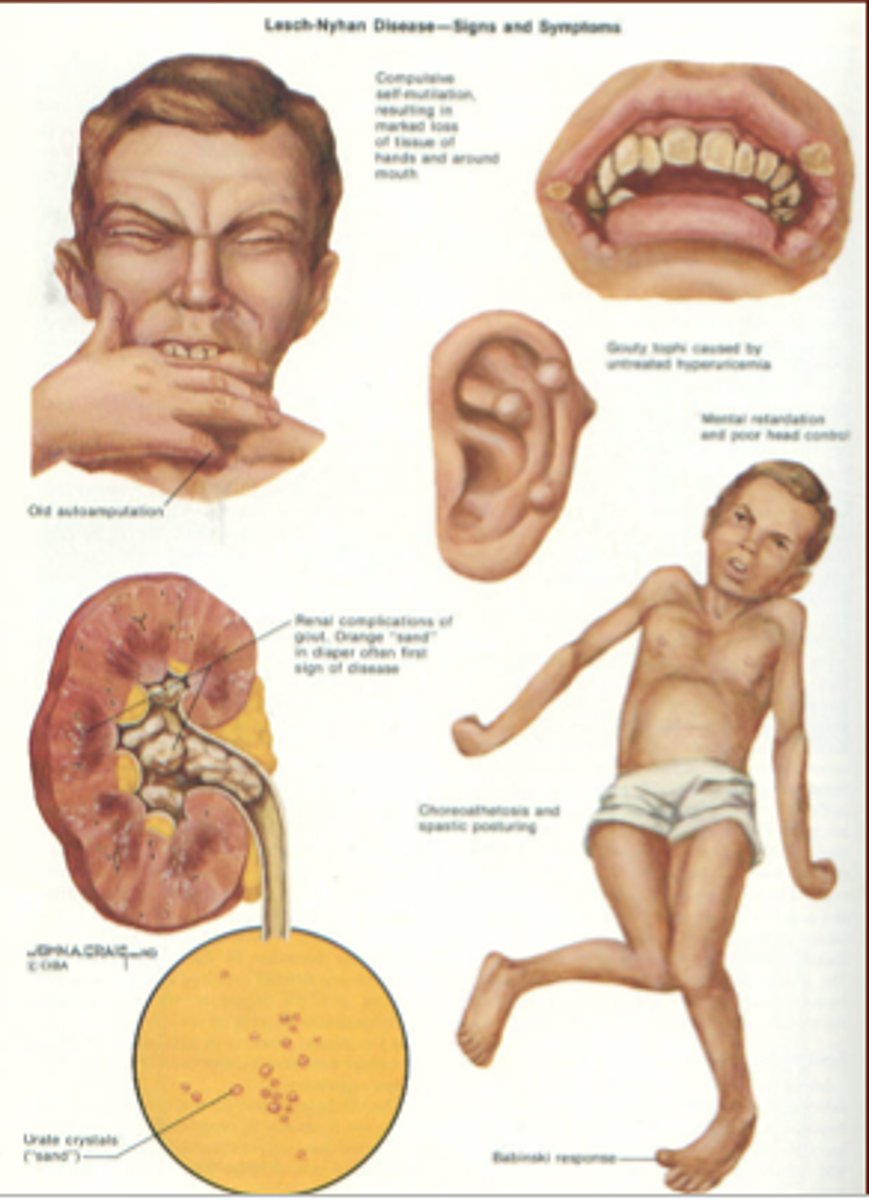

Gout, intellectual disability, self-mutilating behavior in a boy

Lesch-Nyhan syndrome (HGPRT deficiency, X-linked recessive)

Build up of hypoxanthine and guanine

Urate crystals on UA